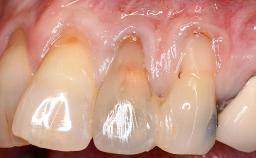

A 30-year-old woman was referred by her general dentist for evaluation of an esthetic complication related to previous implant treatment for congenitally missing maxillary lateral incisors. The patient’s chief complaint was the inadequate esthetic appearance of her smile. The case demonstrates the use of a combined approach to achieve optimal results. Two different flap designs - a tunnel technique and a coronally advanced flap - are employed based on the surgical objectives for the affected site.

Soft Tissue Grafting Yes

Soft Tissue Anatomy Intact Defective